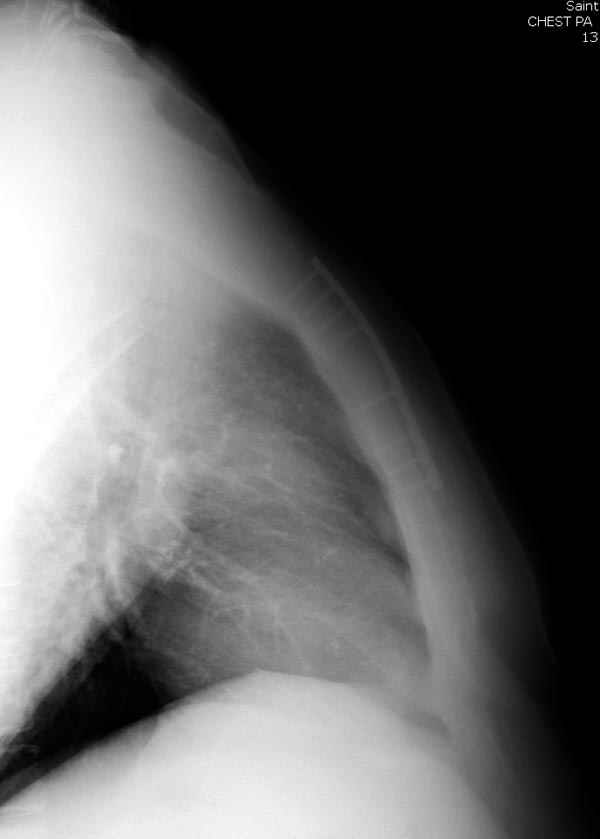

Пару лет назад коллега из грудной хирургии направил больного с хроническими жалобами на боли по поводу ложного сустава грудины.

Оперировали вместе с грудным хирургом и в нашем случае главной причиной была болезненность. Во время операции приняли все меры предосторожности недопущения прокола средостения (см. на 4 снимке близкий контур сердца!!)

Ложный сустав зафиксирован двумя пластинами 2.4 мм (locking plate) позаимствованными из челюстно-лицевой хирургии, с костной пластикой, все остальные пластины мне показались слишком толстыми, грубые для грудины или отсутсвовали возможности создания угловой стабильности.

Рентген снимки во время операции и последние сделаны на днях.